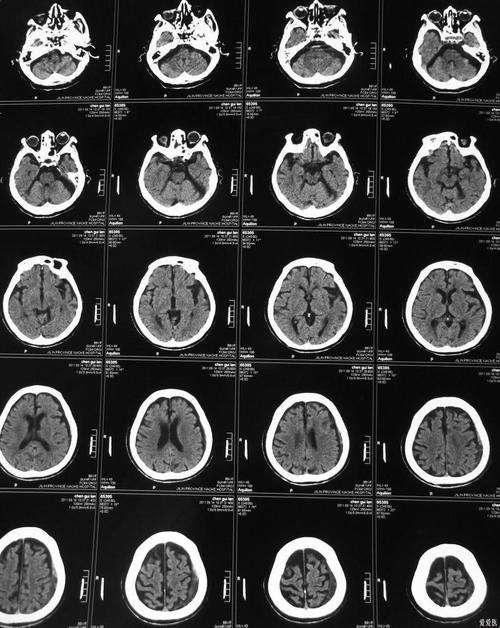

脑梗死的CT检查:基本原理和时间线

要理解怎么看,首先要明白CT在脑梗死不同时期的表现。

如何“看”一张脑CT片子(非专业人士视角)

想象一下,你拿着一张CT胶片或电脑屏幕上的图像,从上到下、从左到右地观察。